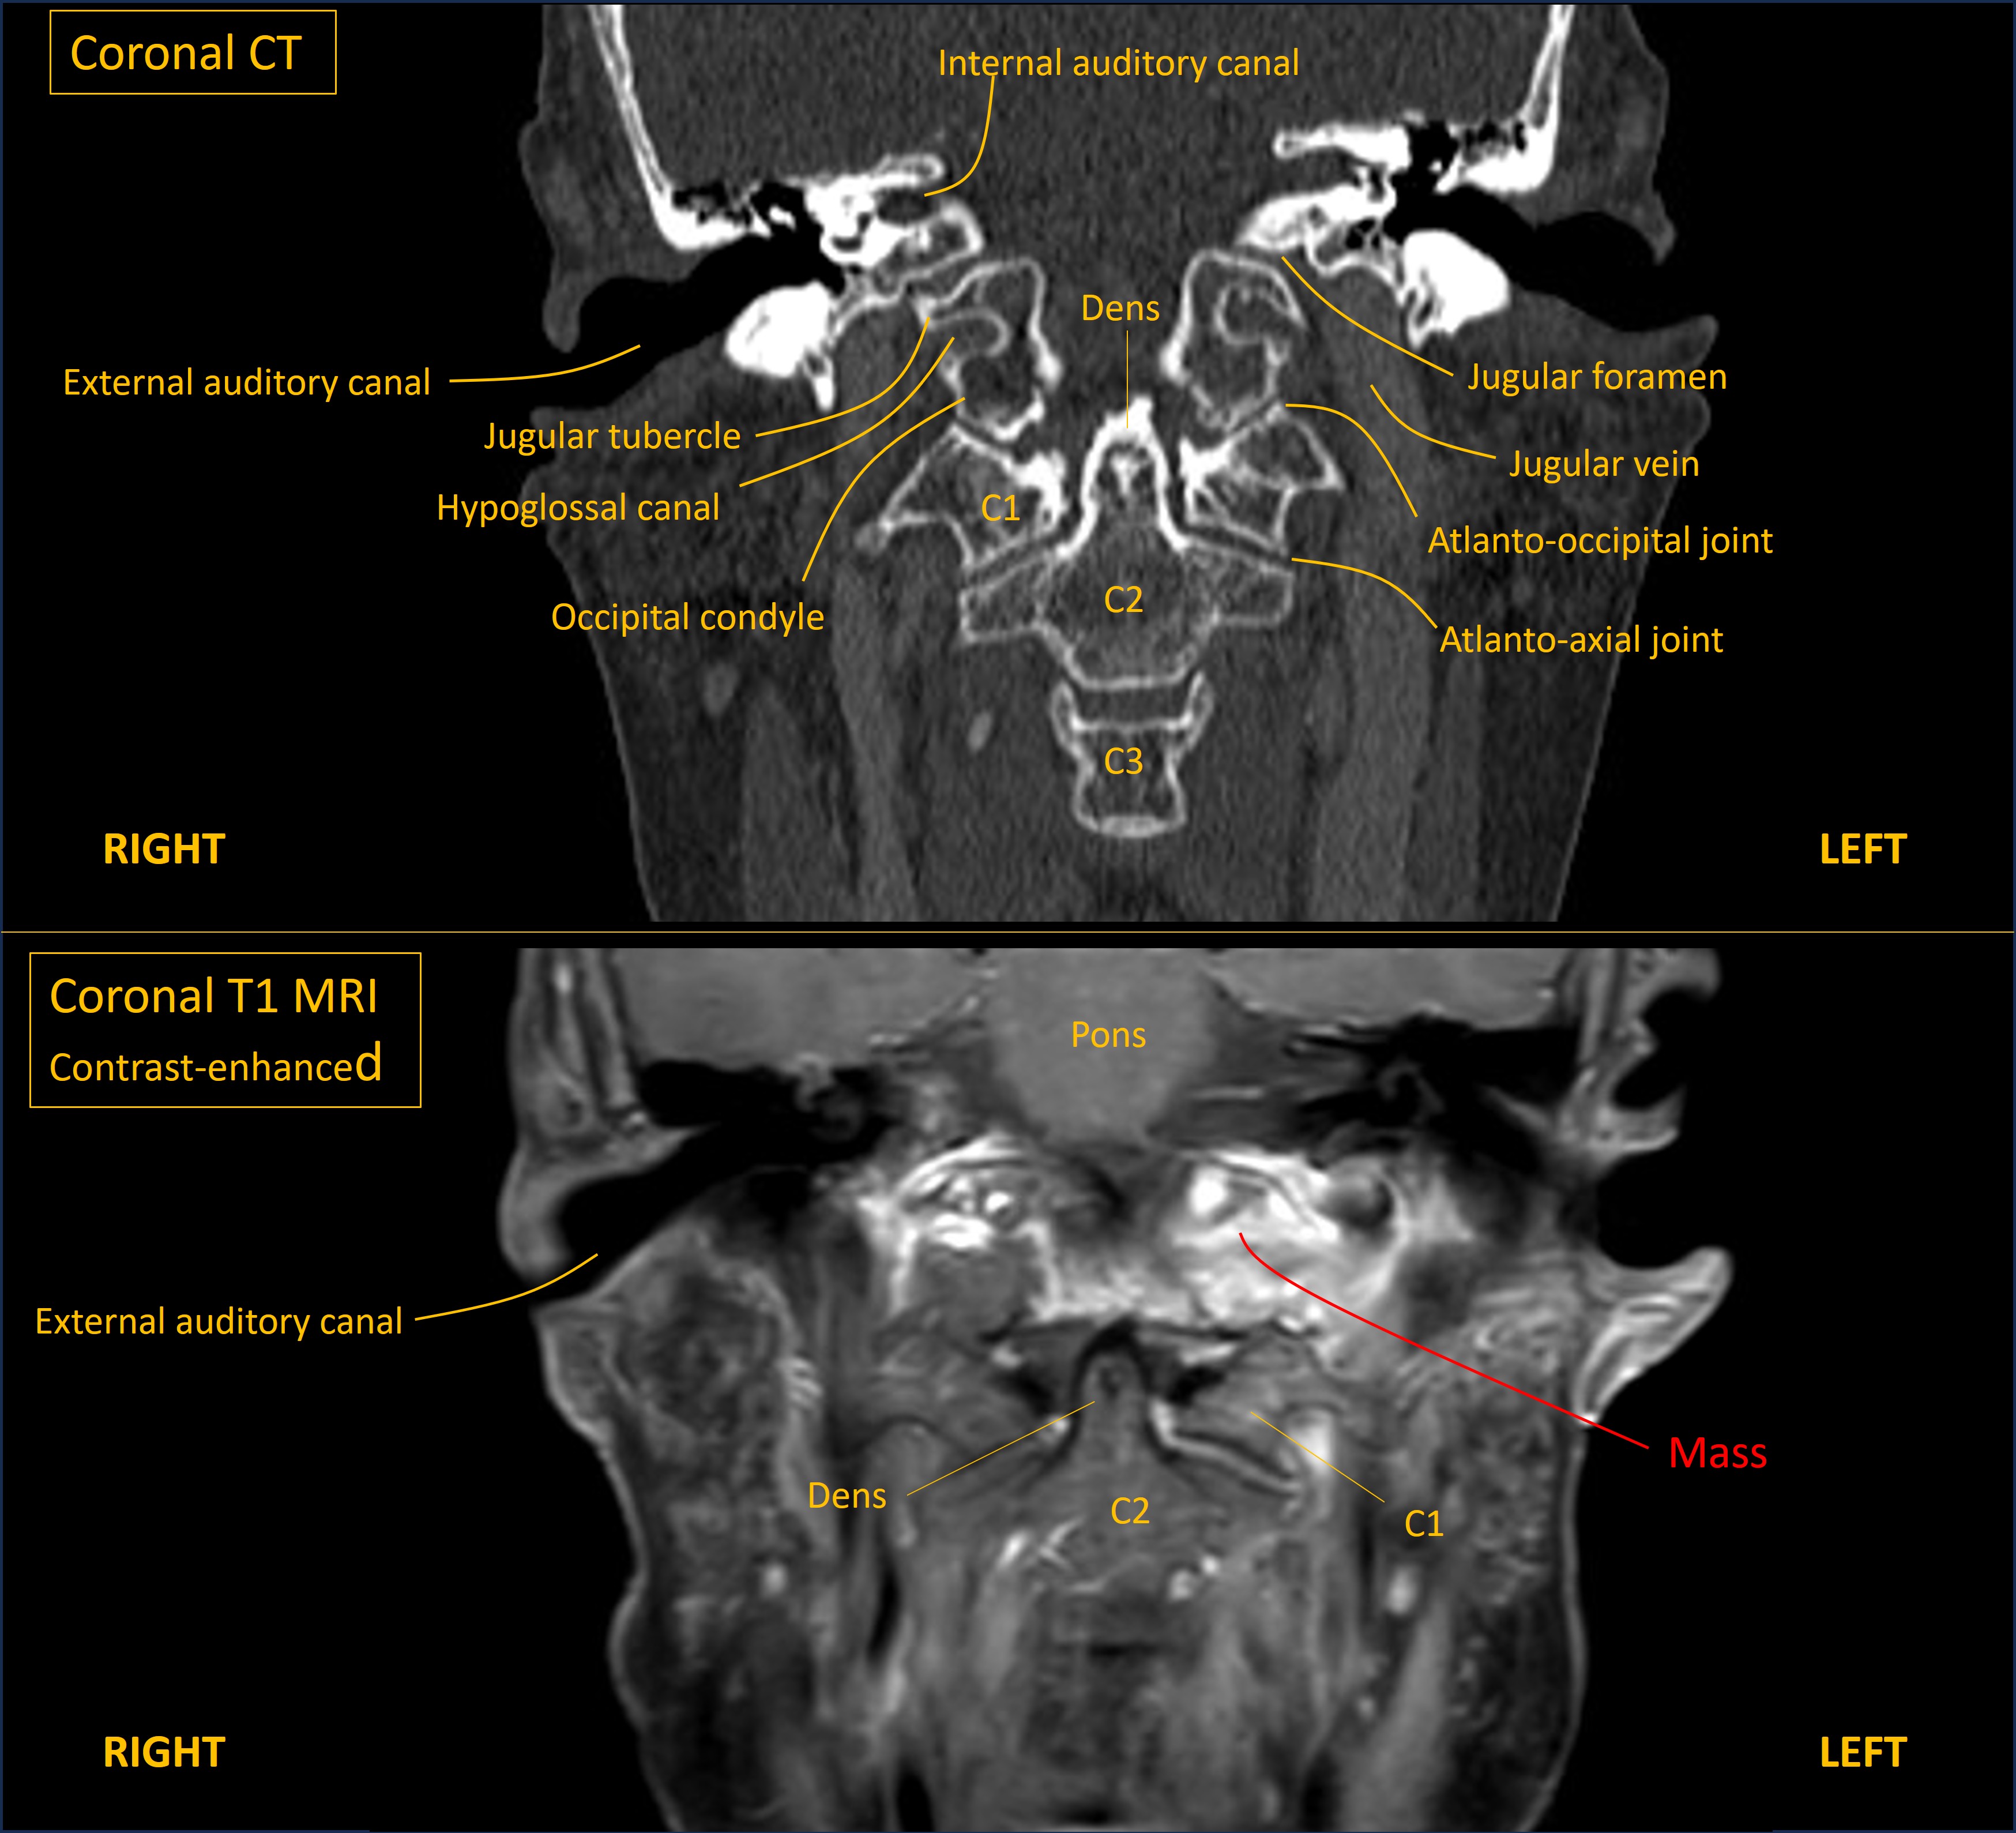

Urgent MRI head, skull base and neck were performed. These showed multiple bony metastases to the skull, including the skull base. A metastatic mass was invading the left occipital bone and affecting the hypoglossal canal, shown on the images below. The CT shows the key anatomy, and the MRI shows the mass:

The left half of the tongue was visibly bright on T2 MRI, indicating oedema due to denervation, and the base was posteriorly displaced due to weakness.